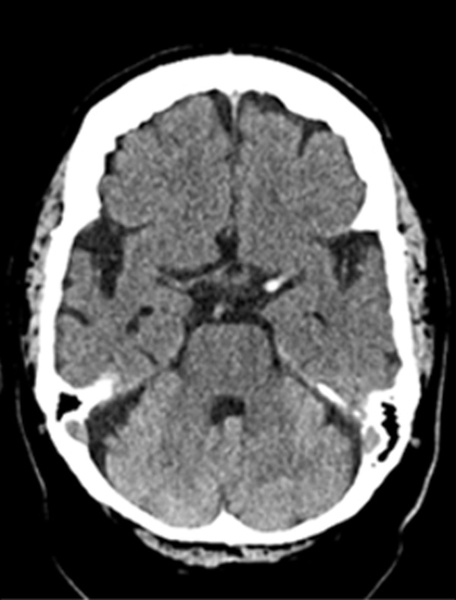

Baseline CT - ASPECTS 10

Baseline CT MCA hyperdensity

Medical imaging CT, CTA